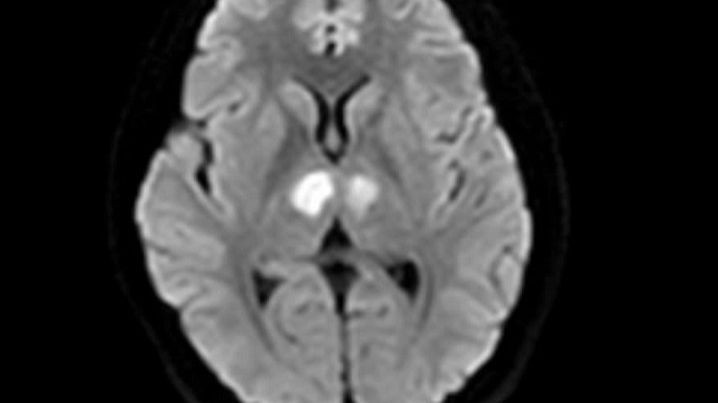

Bệnh nhân không sốt, không co giật, không nôn. Người nhà đưa bệnh nhân đến bệnh viện tư để cấp cứu. Kết quả chụp MRI cho thấy não bệnh nhân có hình ảnh tổn thương vùng đồi thị hai bên. Gia đình xin chuyển bệnh nhân sang Bệnh viện Bạch Mai để được tiếp tục điều trị.